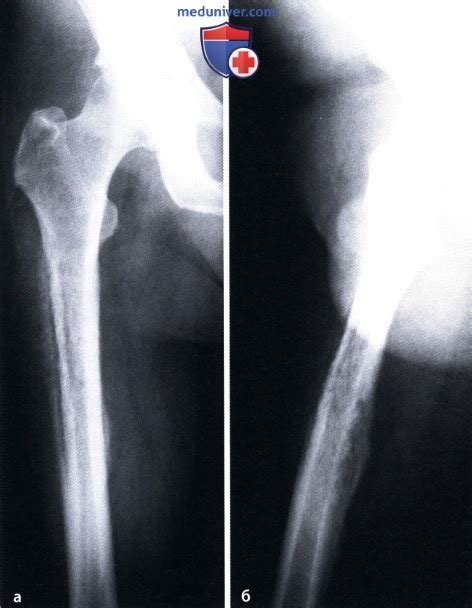

Остеомиелит или остеоид остеома? | Портал радио...